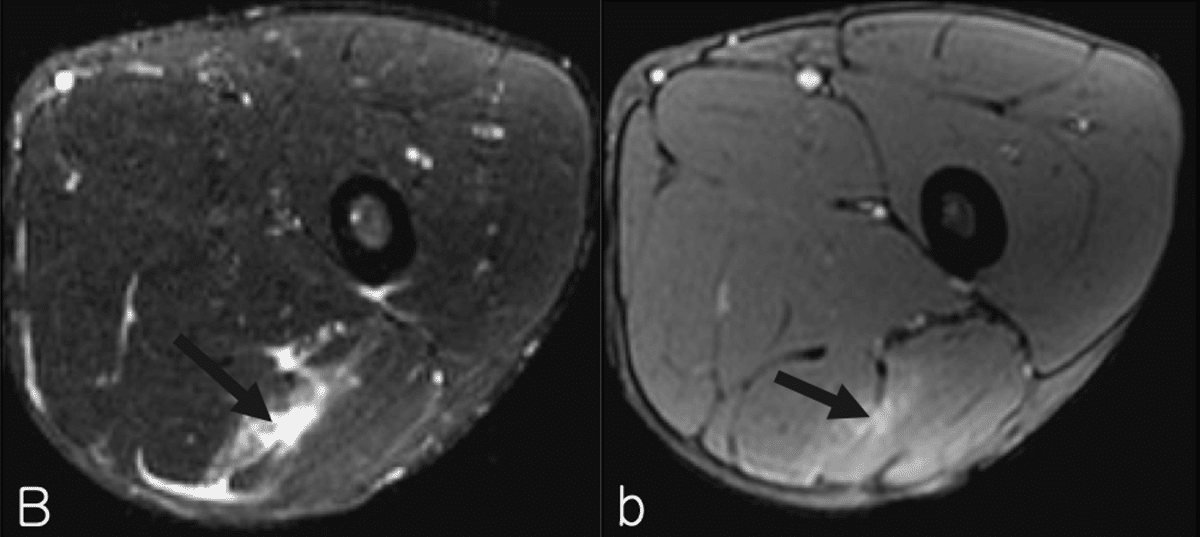

◉Ⅱ型の例

・Ⅱ型1度

(奥脇 透:大腿二頭筋肉ばなれの MRI 分類、臨床スポーツ、2019より引用)